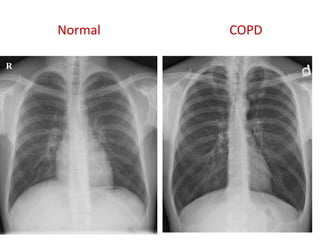

COPD

Normal COPD

R